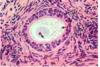

what type of tissue is this?

dense irregular fibrocollagenous tissue

2. dense regular fibrocollagenous tissue

3 compact bone

4. cancellous bone

5. hyaline cartilage

what type of tissue is this?

dense irregular fibrocollagenous tissue

2. dense regular fibrocollagenous tissue

3 compact bone

4. cancellous bone

5. hyaline cartilage